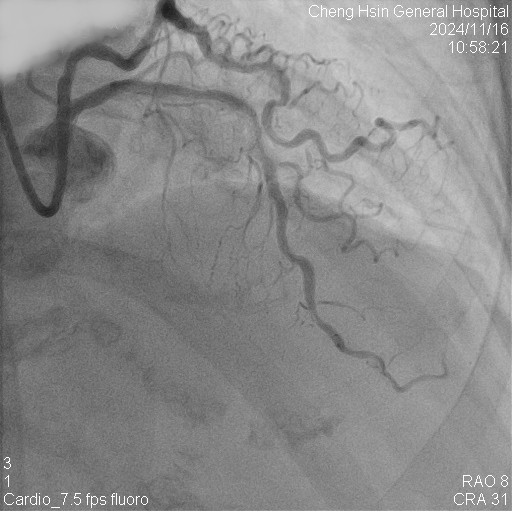

The RCA was calcified but no significantly severe stenosis.The LCX was calcified with mild stenotic lesion and a patent old stent.The LAD was severely calcified with an under-expanded old stent at middle to distal part. The lesion was also severely stenotic. The proximal to middle LAD had moderately stenotic lesion with calcification also.

Initially, we tried to insert IVUS catheter but unable to cross the lesion. We tried a NC balloon but unable to cross it also.Hence, we used rotational atherectomy with 1.5mm burr. However, the burr was unable to cross lesion even in high speed and entrapped in the stent.We removed the burr in guide extension catheter then the NC balloon could cross the lesion. The IVUS cather could also cross it with guide extension catheter support. The stent was almost not expanded. We tried NC balloon high pressure dilation but balloon slippage and burst. The lesion was still un-dilatable. We insert cutting balloon which avoided slippage but remained burst. We escalated the burr size to 1.75mm. The larger burr was not stucked but still unable to cross lesion. Besides, the larger burr causing slow blood flow. After adenosine injection, the patient's blood flow recovered. We reduced the burred size to 1.25mm which cross the lesion once but entrapped while doing polishment. After burr retrieval, we used NC balloon high pressure dilation. The balloon bursted but the lesion remained un-dilatable.Finally, the lithotrypsy balloon could cross the lesion and eliminate 80 pulses. The lesion was expanded much well. The IVUS showed the old stent was expanded and calcium was cracked. We deployed a new stent for old one destruction and proximal dissection. The final IVUS image showed epansion and apposition were accpetable.